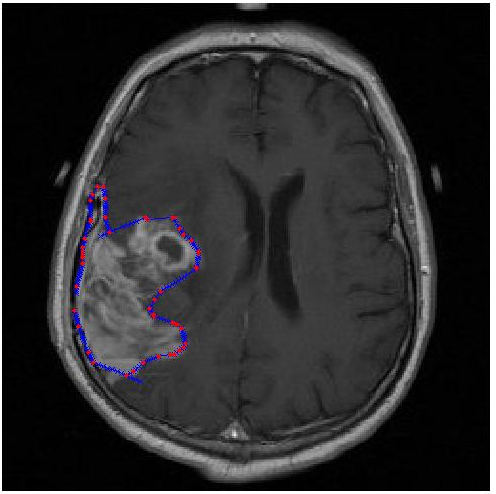

Exercise 5: Fit a contour along a brain tumor

In medical imaging it is common that a person (the radiologist) manually draws a contour around an organ or disease region. This is done with an interface similar to that of an image editor. The person clicks on points on the boundary, and the computer interpolates the boundary segment between the clicks.

The images are located in ~c340/web_docs/labs/labAssign2/brain_tumor.There are

three images:tumor.jpg(real brain MRI image), tumorContour.jpg (tumor actual border, which can be used to measure the error of the polynomial) and polynomialContour.jpg (Polynomial contour of the

tumor. The red dots are given by radiologist and the blue border is fitted to the dots using polynomial interpolation. Note that it serves as an example of what your output would look like).

Fit a piecewise cubic spline curve (Heath Ch7.4.2) along the contour of the brain tumor on the images of exercise. (You can use Octave/Matlab's built in spline or implement the routine yourself).